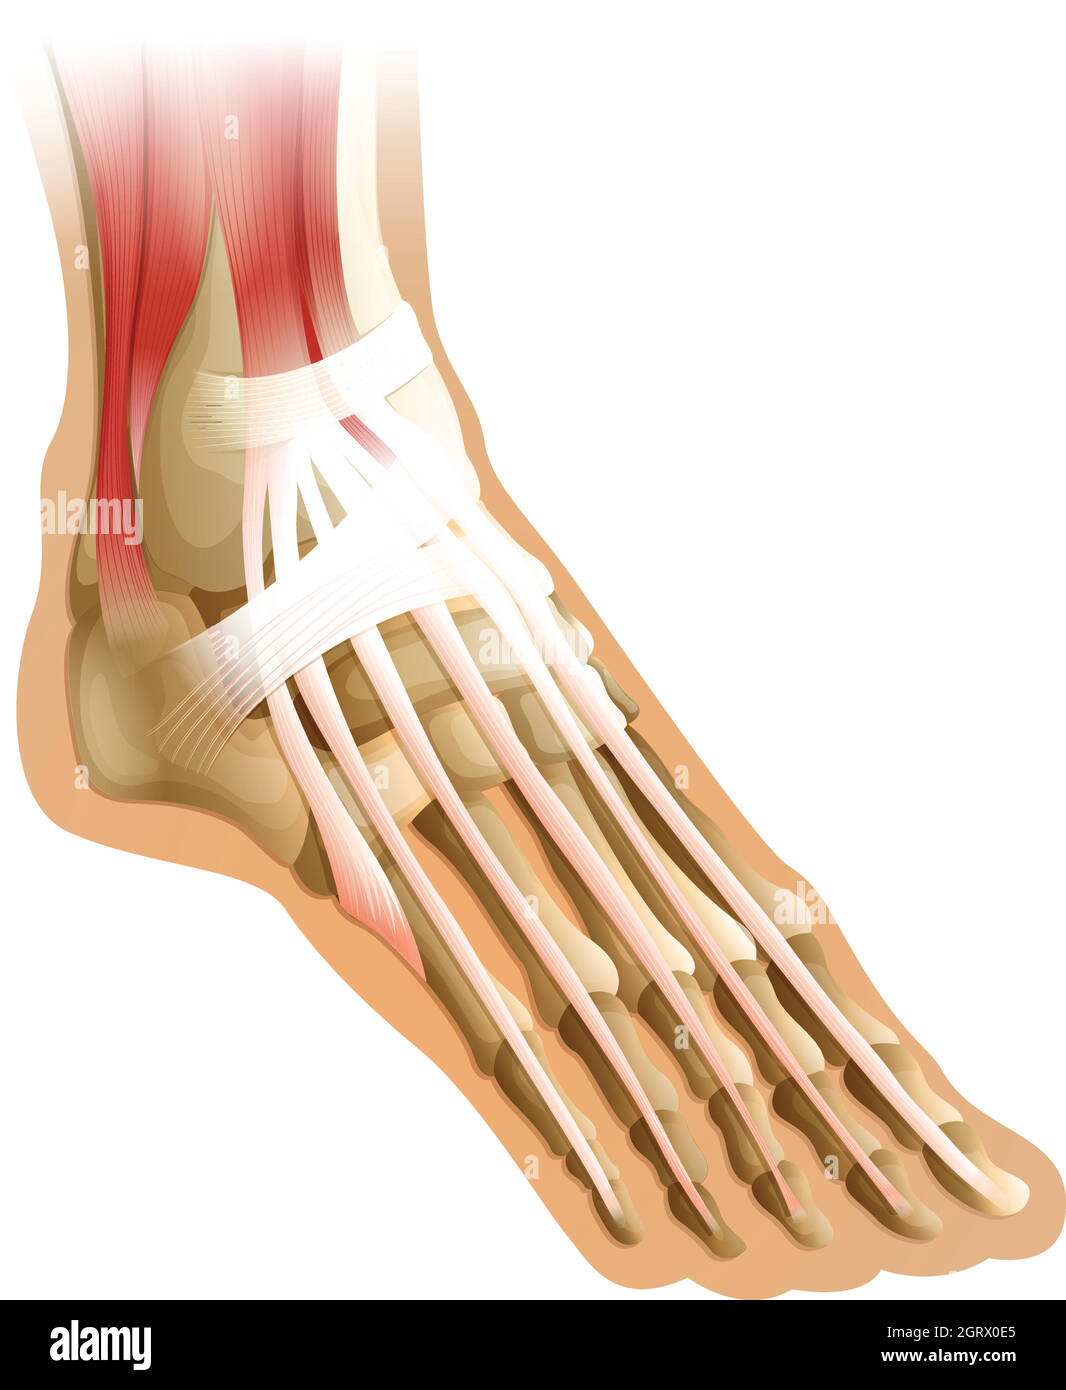

RFTCW7GT–L'articulation de la cheville, les tendons de la cheville anatomie pied eps vector illustration infographie 10

RF2X200ED–L'anatomie de l'articulation de la cheville. Région talocrurale ou os sauteur. Partie du corps humain où le pied et la jambe se rencontrent. Fascia plantaire et tendon d'Achille